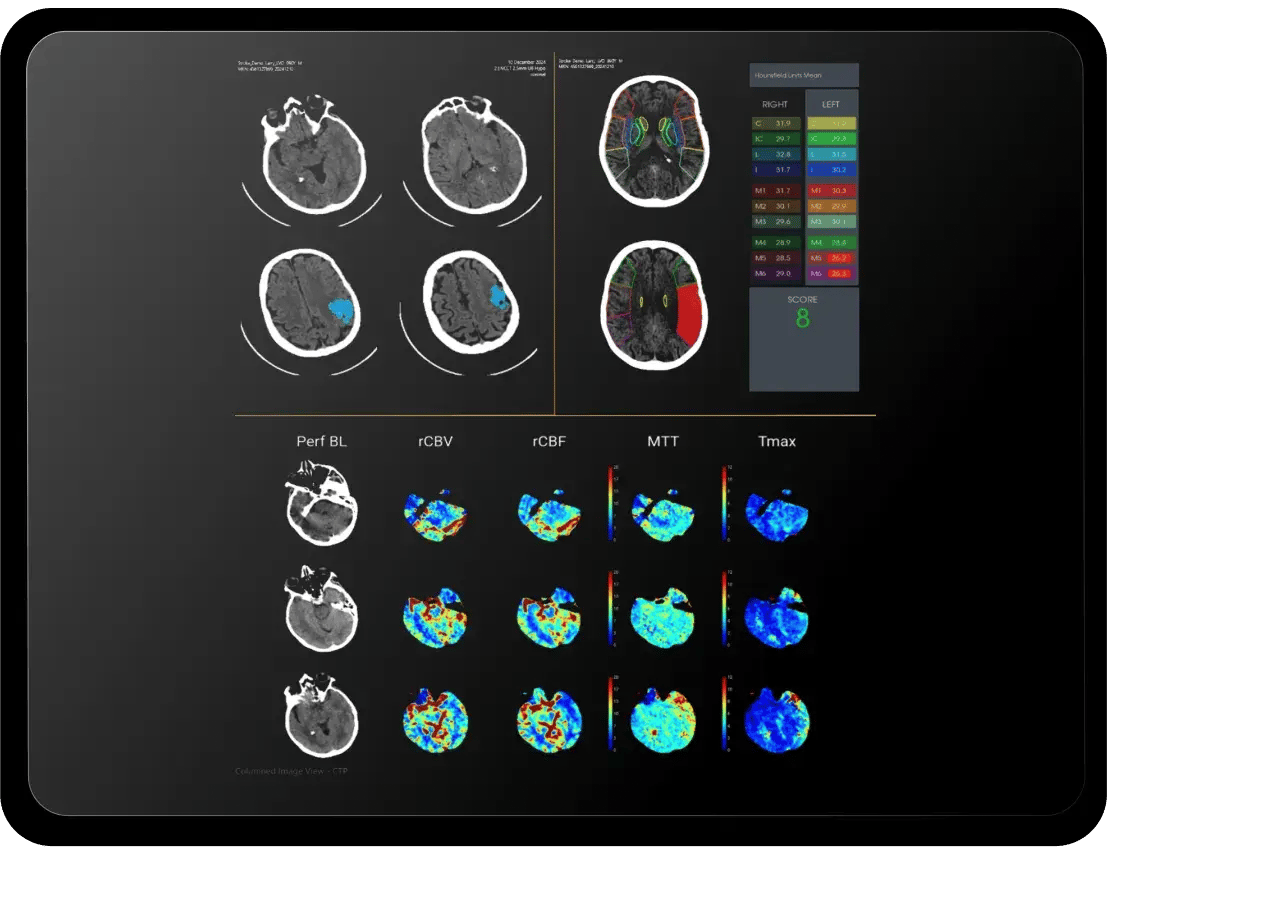

With RapidAI, I can trust that third-party products are vetted with the same clinical rigor as their flagship solutions. This gives me confidence in the platform’s ability to help analyze complex cases with speed and accuracy while catching details that could be easily overlooked in the urgency of the Code Stroke workflow."

Jonathan Clemente, MD FACR

Chief, Department of Radiology at Carolinas Medical Center, Vice President of the Medical Staff and Neuroradiologist at Charlotte Radiology in Charlotte, NC